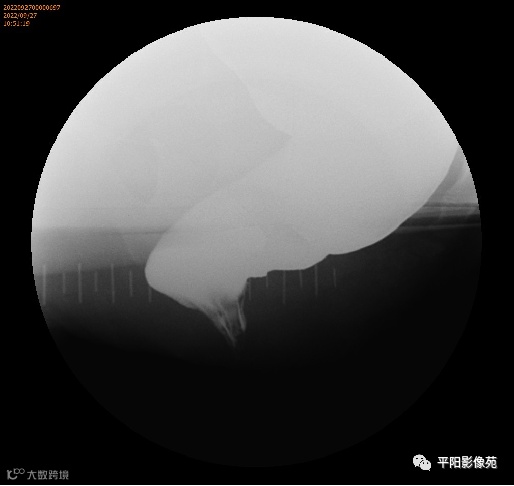

排粪造影

手术

排便造影钡(x射线)排便造影或排便直肠造影是诊断排便障碍的公认临床

工具

。

钡排粪造影实时评估直肠壁形态、盆底运动和排空。